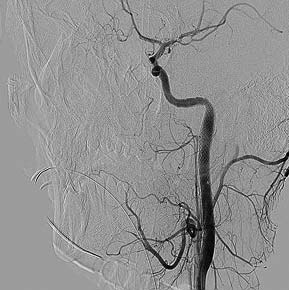

Верифицированный пристеночный тромбоз каменистого сегмента левой ВСА (неровность внутренних контуров, дефекты заполнения; рис. 2) потребовал установки дистальной защиты SpiderFX и стентирования левой ВСА в каменистом сегменте стентом CRISTALLO 7×10×30 мм с последующей постдилатацией (рис. 3).

Рис. 2. Диссекция (неровность внутренних контуров, дефекты заполнения). Установлен стент WALLSTENT проксимальнее области диссекции